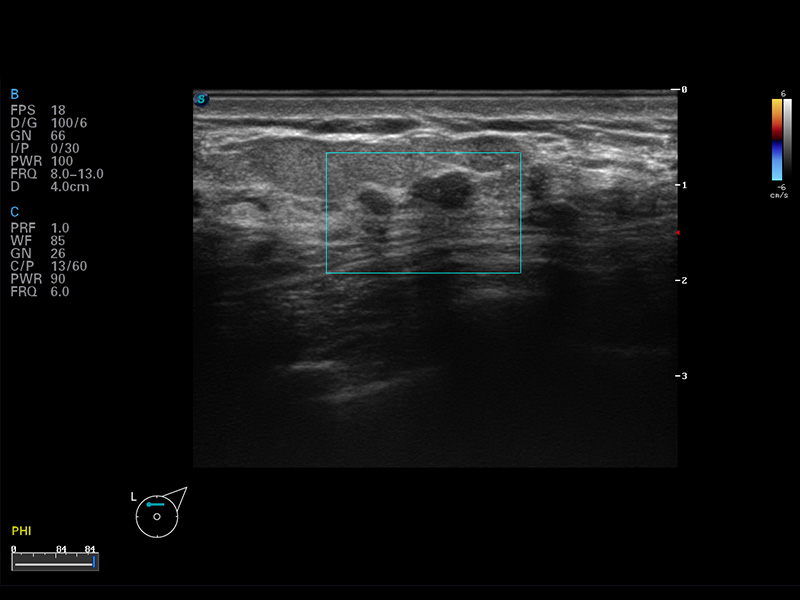

S8 EXP便携式彩色多普勒超声诊断仪是狗万官方网站研发的高端全身应用型便携彩超。高通道的VIS平台融合可视化(Visual)、智能化(Intelligent)和人性化(Smart)的特点,配以狗万官方网站自主研发生产的探头大家族,使您能够快速、准确的获得病人信息,提高工作效率的同时减轻疲劳。

成像技术

多波束形成器

μ-Scan微米成像

谐波成像

空间复合成像